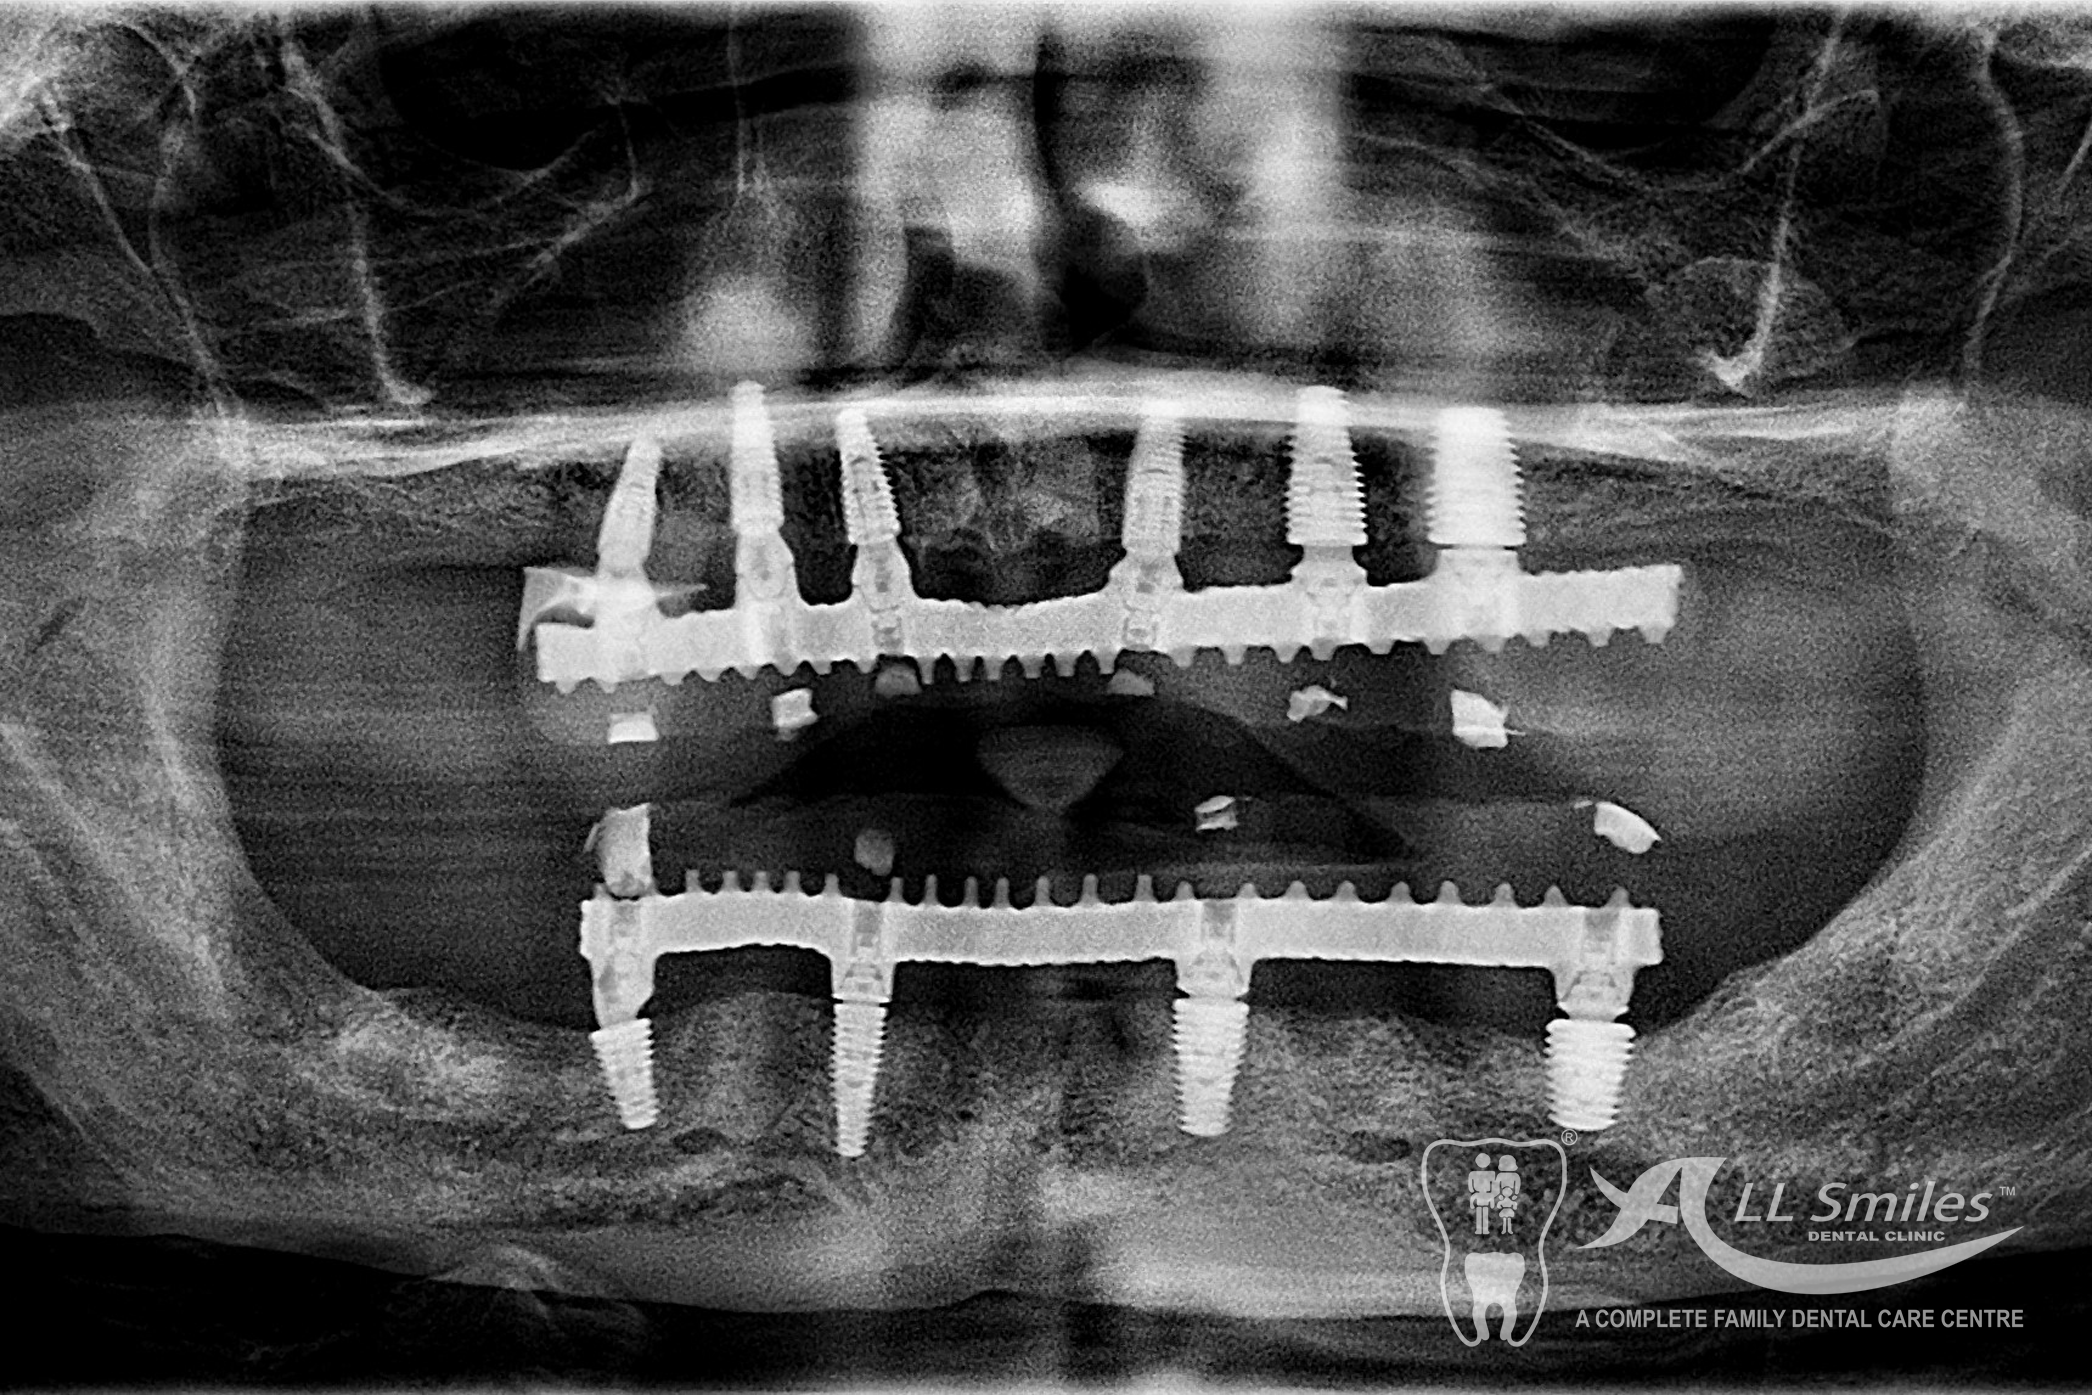

- All on 4 or All on 6: A bridge can be permanently anchored to 4 or 6 implants in your jaw. The Implants for each arch are placed in a single appointment. It is often possible to fix the provisional denture to the new roots at the same time implants are placed in the jaw. You come to the appointment in the practice and leave few hours later with firmly fixed, beautiful teeth. After the healing phase this is replaced by the permanent ceramic or acrylic prosthesis.

A bridge can be permanently anchored to 4 or 6 implants in your jaw. The Implants for each arch are placed in a single appointment. It is often possible to fix the provisional denture to the new roots at the same time implants are placed in the jaw. You come to the appointment in the practice and leave few hours later with firmly fixed, beautiful teeth. After the healing phase this is replaced by the permanent ceramic or acrylic prosthesis.